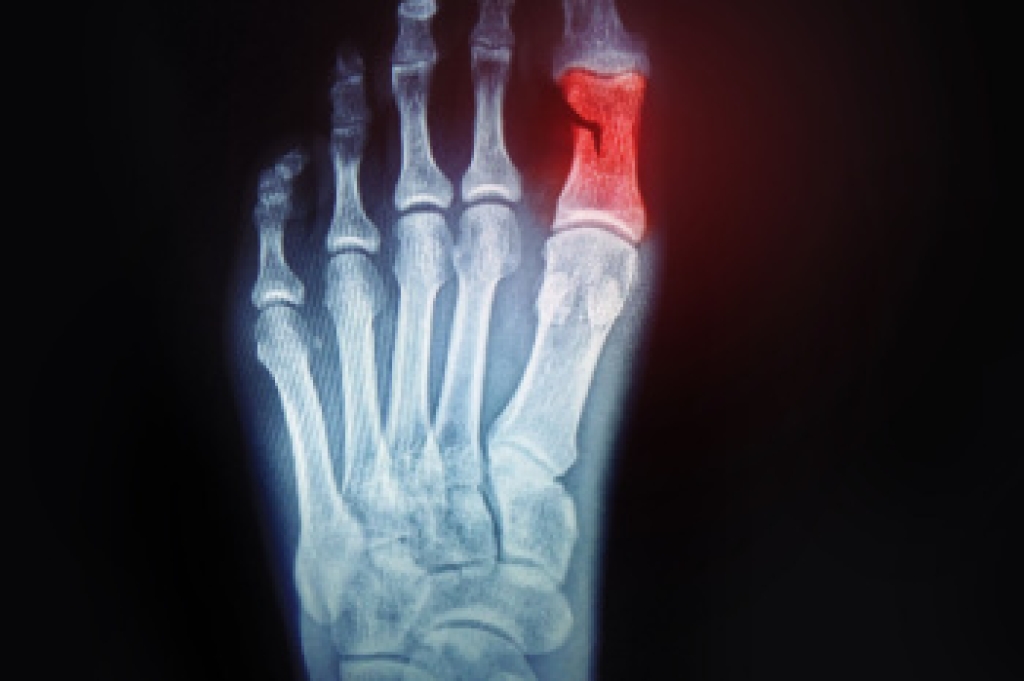

Plantar fasciitis – Pressure and stress that is placed on muscles, joints, and tendons can trigger plantar fasciitis, which is an inflammation of tissue that forms along the bottom of the foot.